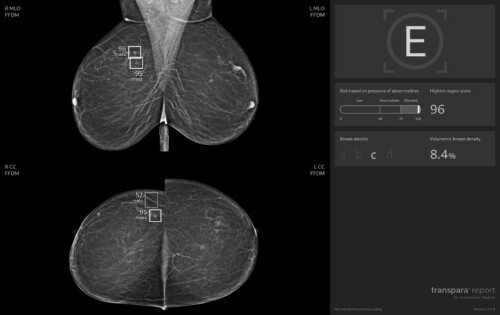

Pilotní projekt využívající umělou inteligenci při vyhodnocování mamografických snímků odstartoval v prvním pololetí 2023 ve spolupráci se zdravotní pojišťovnou OZP a skupinou EUC. Do projektu se jako první zapojilo mamodiagnostické centrum Waltrovka v Praze, které patří mezi nejmodernější v Česku. Vyšetření měly klientky OZP hrazené z fondu prevence jako benefit preventivního programu STOP rakovině prsu.

„Během společného projektu standardně posuzovali každý snímek dva lékaři. Novinkou ale bylo třetí čtení pořízených snímků za pomoci umělé inteligence. Živí odborníci tak získali možnost porovnat svůj nález s doporučením strojového algoritmu, který se učil na milionech snímků uložených v centrální evidenci. Během pilotního projektu jsme si chtěli ověřit, že zapojení AI pomůže snížit riziko přehlédnutí nádorových změn a ulehčí lékařům práci. Podpora a spolupráce s OZP pro nás byla zásadní. Díky ní jsme mohli pacientkám poskytovat vyšetření s využitím AI v běžném provozu a sledovat tak skutečné přínosy i dopady na praxi,“ popisuje prof. MUDr. Jan Daneš, CSc., vysokoškolský profesor a odborník v oboru radiologie a mamodiagnostiky z Mamodiagnostického centra Waltrovka a Beroun, člen skupiny EUC.

Zvýšený zájem o vyšetření se zapojením umělé inteligence při prevenci rakoviny prsu dokládají statistiky loňského a letošního roku Mamodiagnostických center Waltrovka a Beroun. V roce 2024 o něj projevilo zájem 54 % pacientek (celkem 26 481, z toho s využitím AI 14 293), v roce 2025 už se jedná téměř o 74 % (dosud celkem 18 890, z toho AI 13 993). Špičková technologie se tak prakticky během jednoho roku v praxi stala standardem. Lékaři zároveň potvrzují zvýšení záchytu nádorů o zhruba 16,7 %, což odpovídá i výsledkům zahraničních studií.

„Umělá inteligence má mimořádně vysokou přesnost. Negativní prediktivní hodnota dosahuje 99,97 procenta. U naprosté většiny snímků tedy dokáže spolehlivě vyloučit přítomnost nádoru, což snižuje stres a šetří čas pacientek i hodnotitelů,“ popisuje profesor Daneš a doplňuje: „Osobně si nesmírně vážím ještě jedné skutečnosti. Přes počáteční zdrženlivost stoupla důvěra lékařů v technologii během dvou let z 25 % prakticky na 100 %. Dnes už si běžné čtení snímků bez podpory AI neumíme představit.“